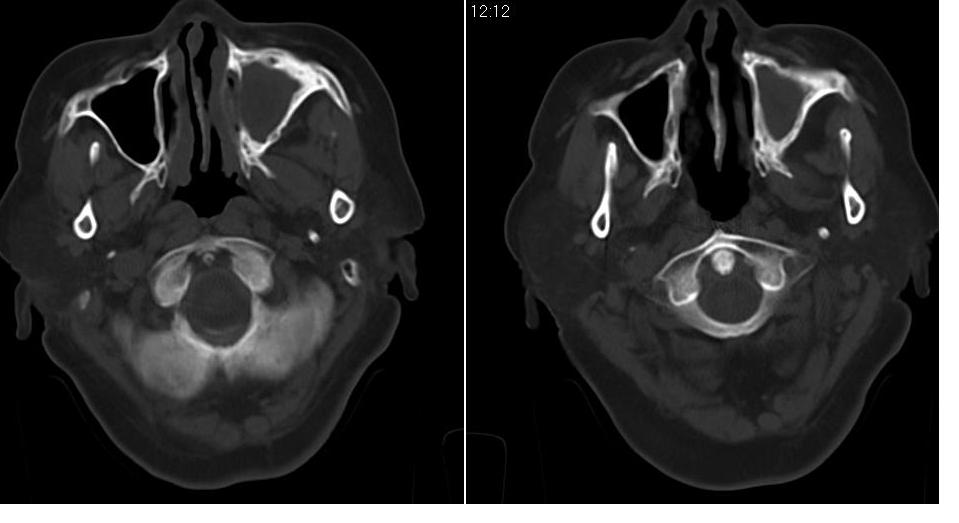

女 70岁,左侧上颌窦腔内肿物。

左侧上颌窦内软组织影,略呈膨胀性,窦壁骨质增生硬化,考虑为黏膜下囊肿.左侧筛窦炎

左侧上颌窦内软组织密度影,窦壁骨质增厚,密度增高,窦口扩大,考虑左侧上颌窦慢性炎症,息肉样变。

左侧上颌窦窦内可见高密度影充填,窦壁增厚,考虑左上颌窦窦囊肿,慢性炎症.